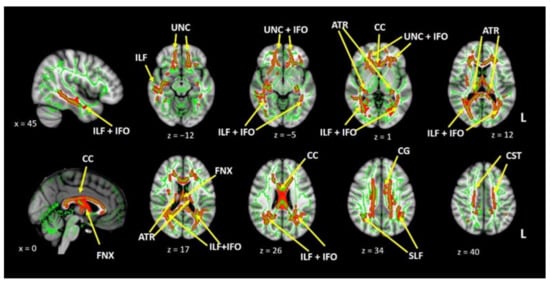

3.2.3. Diffusion Tensor Imaging

3.2.4. Vertex Analysis and Thalamic Parcellation